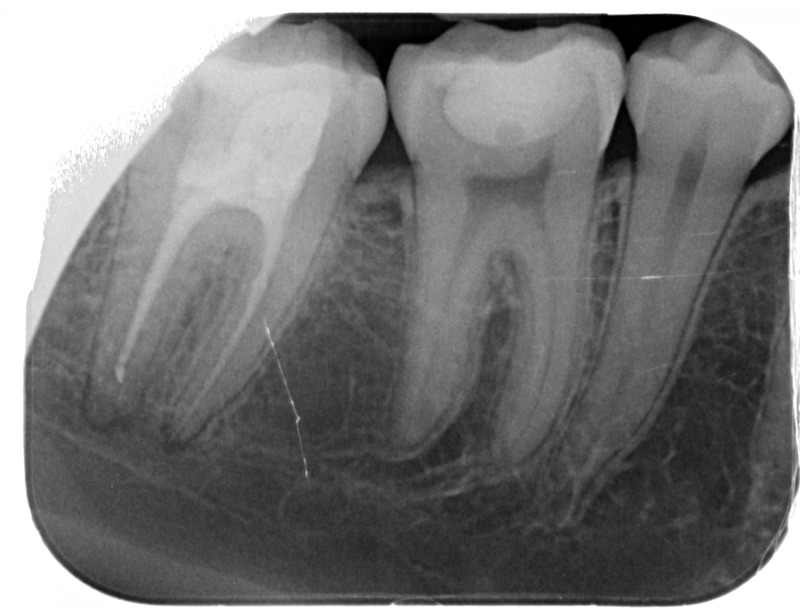

• Reprise de traitement endodontique : La manœuvre consiste à retourner à l’intérieur des racines d’une dent déjà traitée. Il arrive occasionnellement qu’une nouvelle inflammation se déclare suite à une reprise de carie ou une fracture de la dent, ou si le premier traitement endodontique est incomplet. Après s’être assuré que la dent lésée était conservable, il convient de désinfecter de nouveau le réseau canalaire parfois très complexe. La nouvelle obturation des canaux devra être protégée aussi rapidement que possible pour éviter une éventuelle contamination bactérienne.

Après